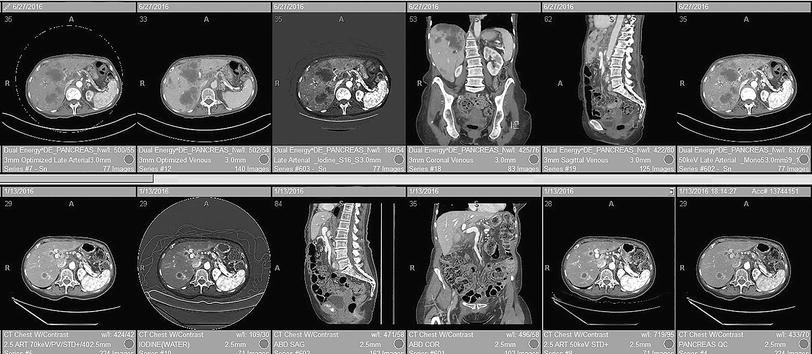

Let’s look at a specific example: hanging protocols. Hanging protocols are the rules a viewer uses to load and arrange images (e.g. what series appears where, which prior image sits side-by-side, and what window/level presets apply for each modality and body part). In practice they’re brittle. The vendors implement the DICOM standard differently, sometimes it’ll pull up the wrong comparison image, etc. Radiologists waste a lot of time fixing these issues and setting up the images in the way they prefer to make a diagnosis. These seconds per case compound into hours per shift and higher cognitive load, and a workflow software can make a big difference.

A smarter worklist and viewer can automatically surface the most relevant prior, apply site- and modality-specific layouts with sensible presets, inline voice-to-structured dictation that pre-populates required fields and drops an impression scaffold in the radiologist’s style, and flag missing checklist items like laterality, comparison dates, and critical-result routing before sign-off. Basically making sure the images are loaded up right and to the radiologists individual workflow preference.